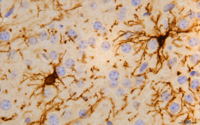

Unsere Arbeitsgruppe ist die erste weltweit, die dieses starke Nervengift extrem verdünnt direkt im Gehirn anwendet, um Symptome der Parkinson’schen Erkrankung zu behandeln. BoNT-A wird durch uns bei einem Rattenmodell der Parkinson’schen Erkrankung in ein Gehirngebiet injiziert, das unter der Erkrankung übersteuert ist – das Striatum. Diese Überaktivität des Striatums resultiert unter Anderem aus einer zu starken Ausschüttung des Botenstoffs Acetylcholin. Botulinumneurotoxin-A (BoNT-A) blockiert die Freisetzung von Acetylcholin. In der Vergangenheit wurden durch uns schon viele spannende und erfolgversprechende Erkenntnisse zu dieser experimentellen Behandlung gewonnen.

Es war das Ziel dieser Arbeit herauszufinden, ob und wohin sich BoNT-A nach einer solchen Behandlung im Gehirn ausbreitet. Außerdem sollte untersucht werden, wie lange BoNT-A im Gehirn seine Wirkung entfaltet. Die Gehirne von BoNT-A-behandelten Ratten wurden mittels spezieller Färbemethoden und mikroskopischer Analysen vermessen. Wir konnten nachweisen, dass BoNT-A nicht an seiner Injektionsstelle verbleibt, sondern im Gehirn weitergereicht wird. Dies geschieht durch spezielle Transportprozesse von Nervengewebe, dem axonalen Transport. Außerdem konnten wir auch ein Jahr nach einer solchen Behandlung noch eine Aktivität von BoNT-A in den Gehirnen nachweisen, das heißt, dass selbst ein Jahr nach einer Injektion von BoNT-A in das Gehirn, dieses Toxin noch nicht vollständig abgebaut worden ist.